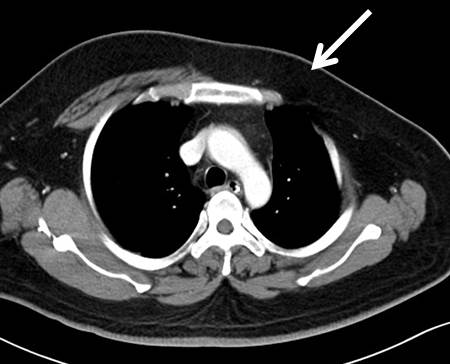

Poland’s Syndrome-CT - Sumer’s Radiology Blog

www.indianradiology.comsyndrome radiology

www.indianradiology.comsyndrome radiology

LearningRadiology - Poland, Syndrome

learningradiology.comsyndrome poland learningradiology here arrows left muscle same without click